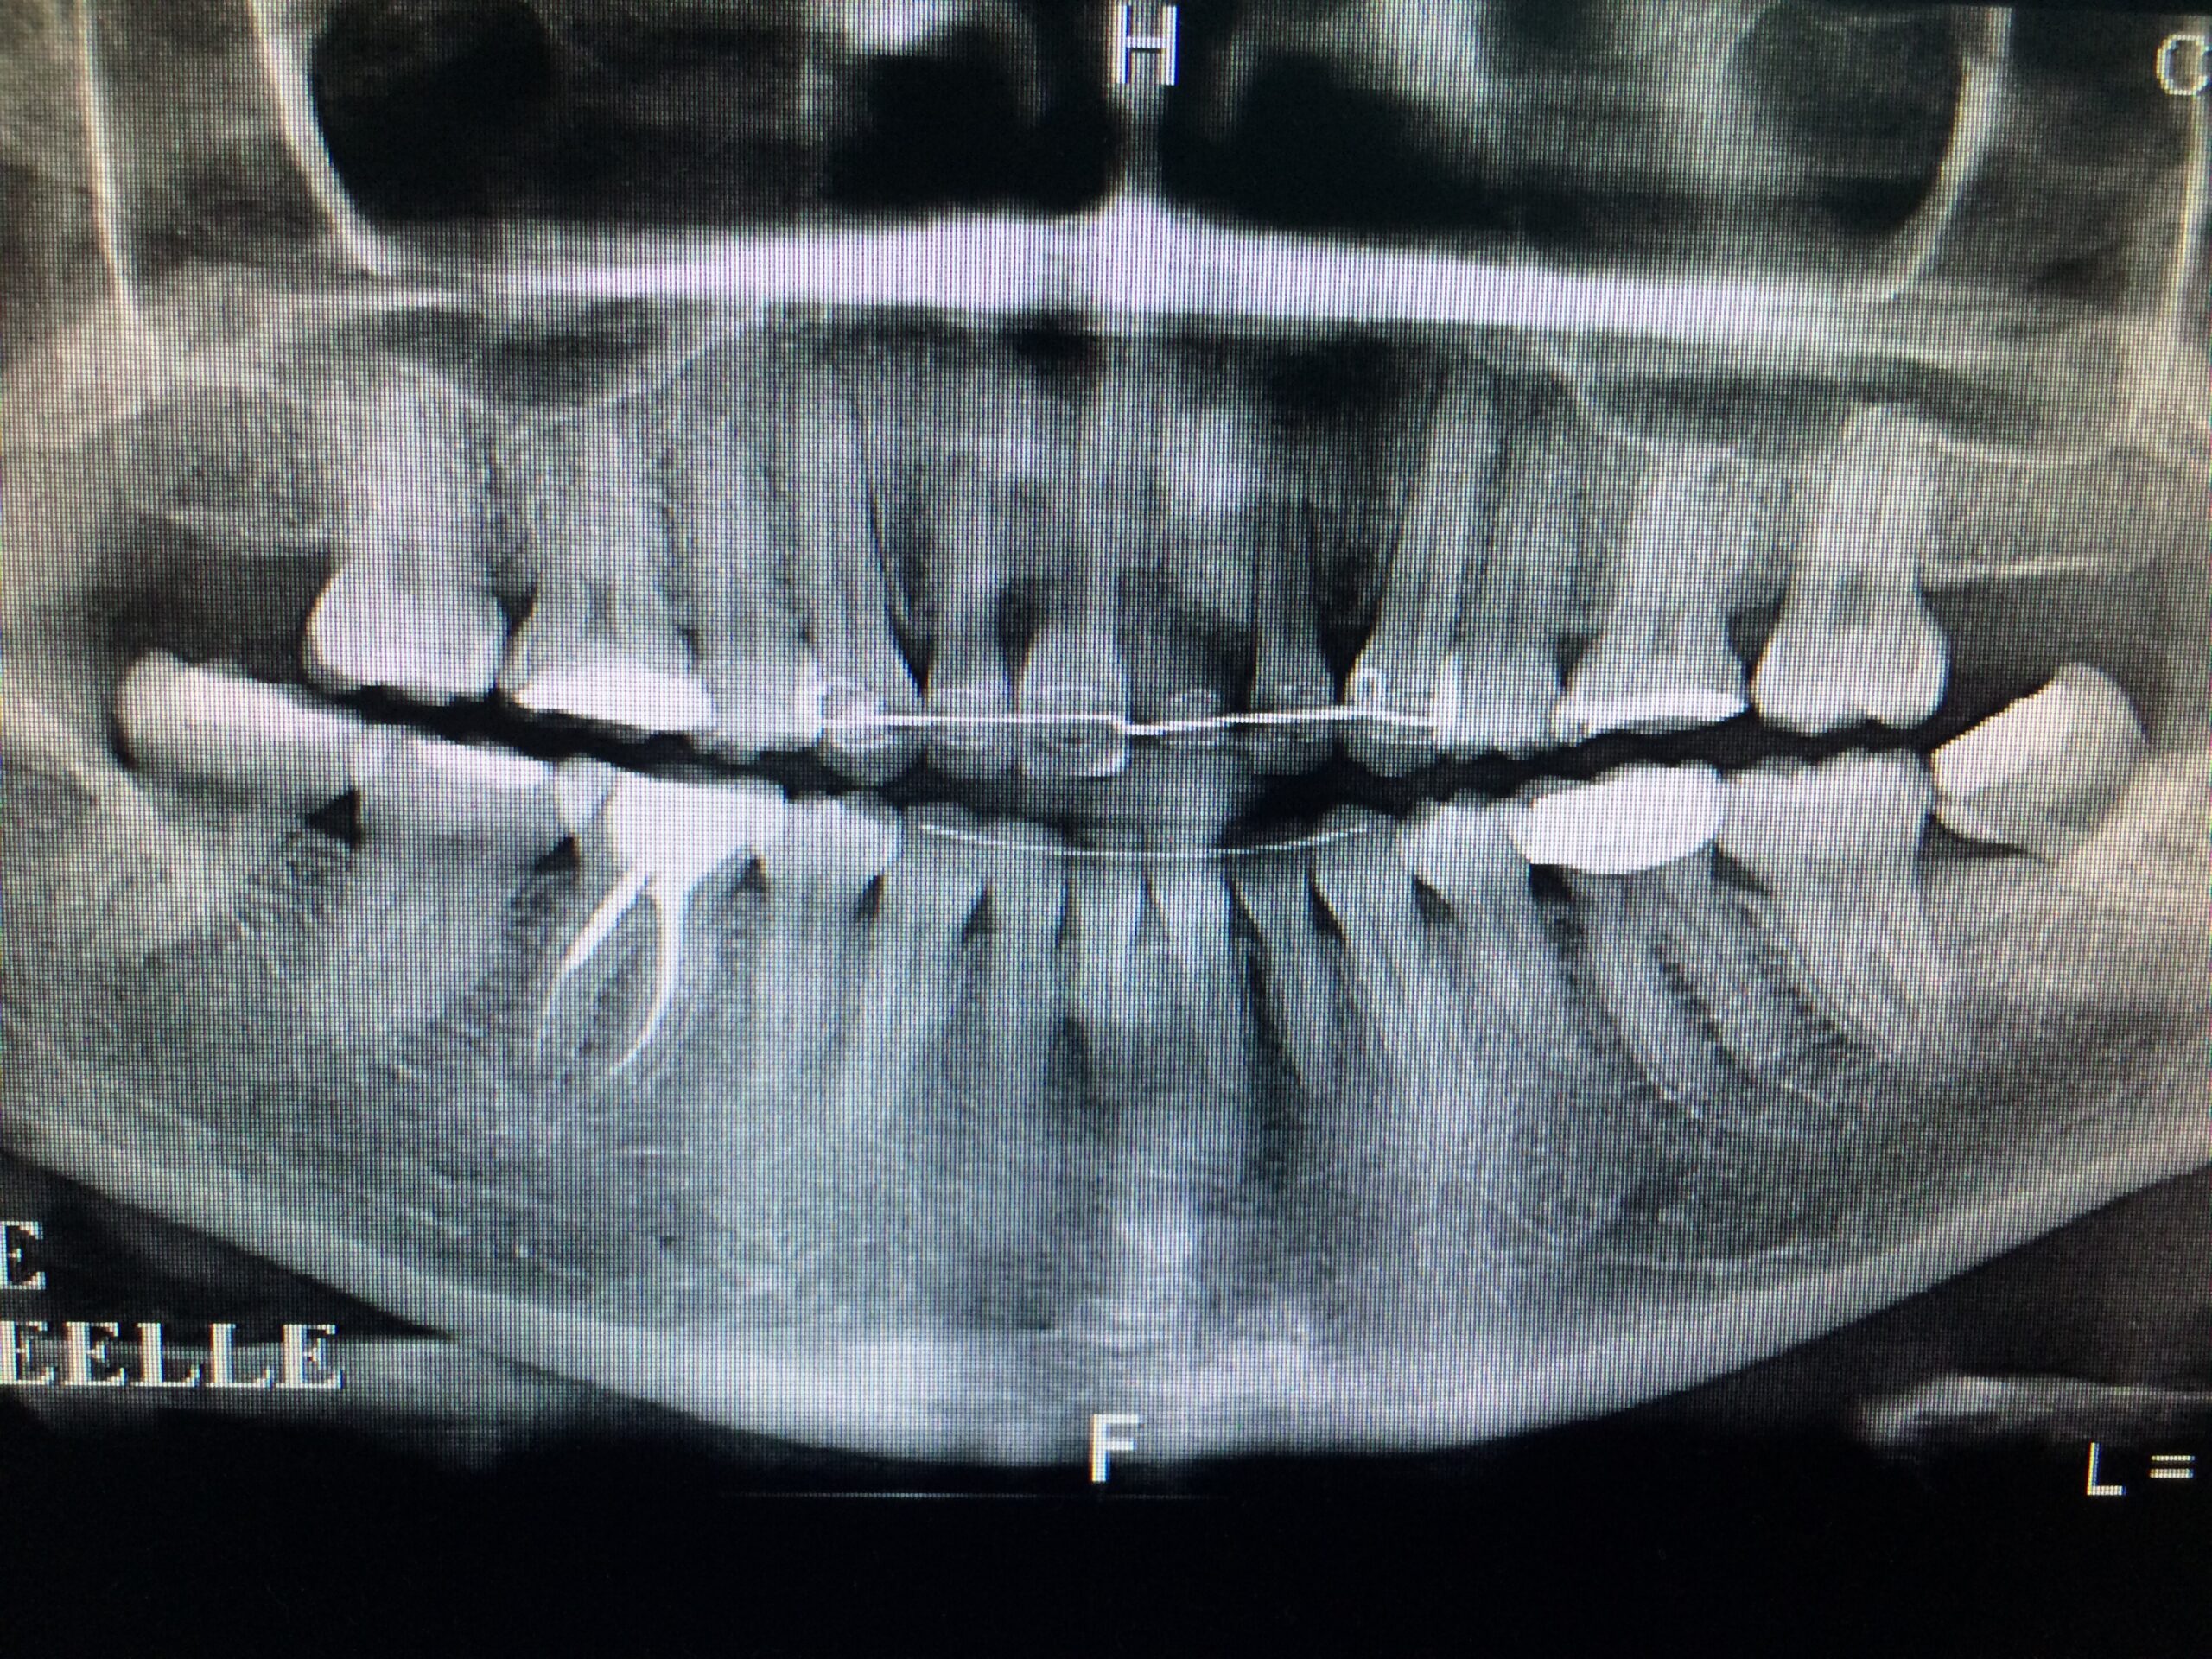

Un implant dentaire est une racine artificielle en titane qui remplace la racine manquante d’une dent naturelle. Il est placé dans la mâchoire inférieure ou supérieure pour remplacer une ou plusieurs dents. Après la période de cicatrisation osseuse, la couronne est fixée au-dessus de l’implant.

La pose d’un implant dentaire s’effectue en plusieurs étapes étalées sur quatre à neuf mois, et en règle générale, de la façon suivante :

La durée totale du traitement dépend de plusieurs facteurs. Il est déterminé en fonction du nombre de dents à remplacer, du volume osseux, de l’état général du patient. En général, il faut entre 3 et 9 mois.

- Implant unitaire

- Les implants encastrés

- La Réhabilitation implantaire totale

- Les implants distaux

- Les implants sinusien

- La chirurgie implantaire guidée